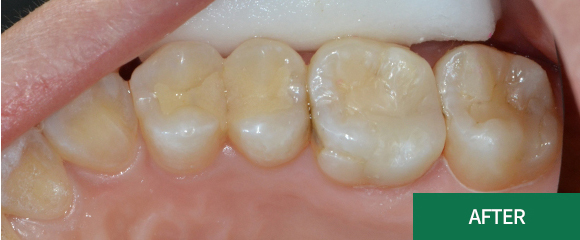

충치치료

레진

인레이

크라운